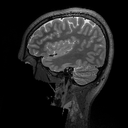

This result implies that random noise can also produce undesirable effects. In Fig. 3 we show several examples of this effect. For the first DL method, mean zero Gaussian noise causes the NN reconstruction map to hallucinate, by artificially removing an image feature (indicated by the red arrow). In the second case, certain image independent, small mean Gaussian noise causes severe instabilities in the recovered image. Notice that the noise causes the second DL method to exhibit completely nonphysical artefacts, which could be easily identified by a practitioner as a failure mode. Yet for the first method it creates seemingly realistic artefacts (hallucinations). Such pernicious artefacts may be impossible to detect.

Hallucinations with zero-mean Gaussian noise Instabilities w.r.t. to Gaussian noise with image independent mean

Noisy image: Noisy image:

|x+v|𝑥𝑣|x+v| |x+v|𝑥𝑣|x+v|

(full size) (cropped)

Refer to caption Refer to caption

DeepMRI-net: DeepMRI-net:

|Ψ(A(x+v))|Ψ𝐴𝑥𝑣|\Psi(A(x+v))| |Ψ(Ax)|Ψ𝐴𝑥|\Psi(Ax)|

(cropped) (cropped)

\begin{overpic}[width=433.62pt]{plots/im_noise1_fact_3_rec_worst_100_place_2_crop.png} \put(68.0,42.0){\color[rgb]{1,0,0}\definecolor[named]{pgfstrokecolor}{rgb}{1,0,0}\vector(1,4){6.0}} \end{overpic} Refer to caption

AUTOMAP: AUTOMAP:

Ψ(Ax+e0)Ψ𝐴𝑥subscript𝑒0\Psi(Ax+e_{0}) Ψ(Ax+e1)Ψ𝐴𝑥subscript𝑒1\Psi(Ax+e_{1})

(full size) (full size)

Ψ(Ax+e2)Ψ𝐴𝑥subscript𝑒2\Psi(Ax+e_{2}) Ψ(Ax+e3)Ψ𝐴𝑥subscript𝑒3\Psi(Ax+e_{3})

Figure 3: (Hallucinations and instabilities due to random noise) Two DL methods exhibit hallucinations and instabilities due to random noise. On the left, the DeepMRI-net [66] reconstruction map is unstable to mean-zero Gaussian noise v𝑣v. In this case, the NN hallucinates by removing a key image feature (see the red arrow). On the right, the AUTOMAP [82] reconstruction map is unstable to Gaussian noise. The noise vector e0subscript𝑒0e_{0} is drawn from a zero-mean Gaussian distribution, whereas the mean of the distribution, used to generate e1,e2subscript𝑒1subscript𝑒2e_{1},e_{2} and e3subscript𝑒3e_{3}, is based on three worst-case noise vectors computed for AUTOMAP with respect to a different image. This makes the mean is image independent. As we can see, the instability of the map produces noticeable artefacts. The measurement matrix in these experiments is a subsampled Fourier transform with 33% (left) and 60% (right) subsampling, respectively. See §A for further information.